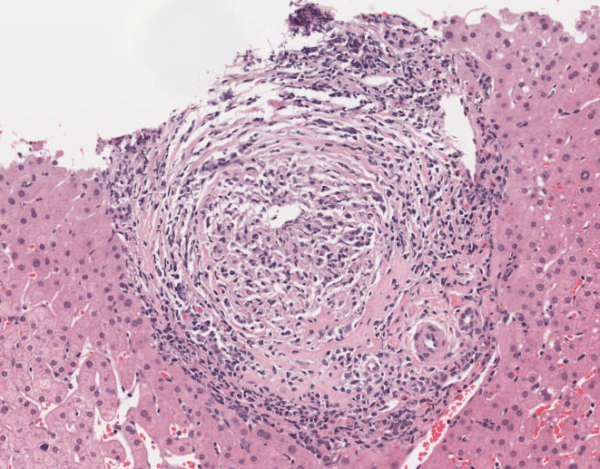

Aunque la biopsia hepática no es estrictamente necesaria para el diagnóstico de la colangitis biliar primaria, salvo en los casos en los que los anticuerpos antimitocondriales estén ausentes, sigue siendo una herramienta útil para evaluar la extensión del daño hepático y la estadificación histológica de la enfermedad. La biopsia hepática permite clasificar la enfermedad en diferentes estadios, según los hallazgos histológicos observados. El estadio I se caracteriza por la presencia de inflamación portal acompañada de granulomas, estructuras inflamatorias típicas de la enfermedad. El estadio II muestra una proliferación de conductos biliares y inflamación periportal, es decir, alrededor de los conductos biliares. En el estadio III, se observan septos fibrosos interlobulillares, que son signos de fibrosis avanzada en el hígado. Finalmente, el estadio IV corresponde a la presencia de cirrosis, que es el daño hepático irreversible debido a la fibrosis extensa y la formación de nódulos hepáticos.

La sarcoidosis es una enfermedad inflamatoria multisistémica que se caracteriza por la formación de granulomas en varios órganos, incluidos el hígado y los conductos biliares. Aunque la sarcoidosis puede causar colestasis y anomalías en las pruebas de función hepática, la presencia de granulomas en el hígado es un hallazgo distintivo que la diferencia de la colangitis biliar primaria. Además, en la sarcoidosis, los granulomas son generalmente no caseosos, lo que los distingue de otras causas inflamatorias hepáticas.